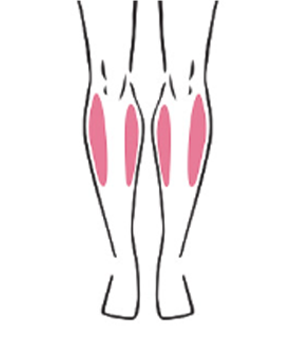

ハピス超音波ふくらはぎ形成術の特徴

一度の精密施術で、構造を可視化しながら矯正します。

ハピスの超音波ふくらはぎ形成術は、高解像度医療用超音波機器を用いて、施術前・中・後の全過程をリアルタイムで確認します

筋肉の厚さ